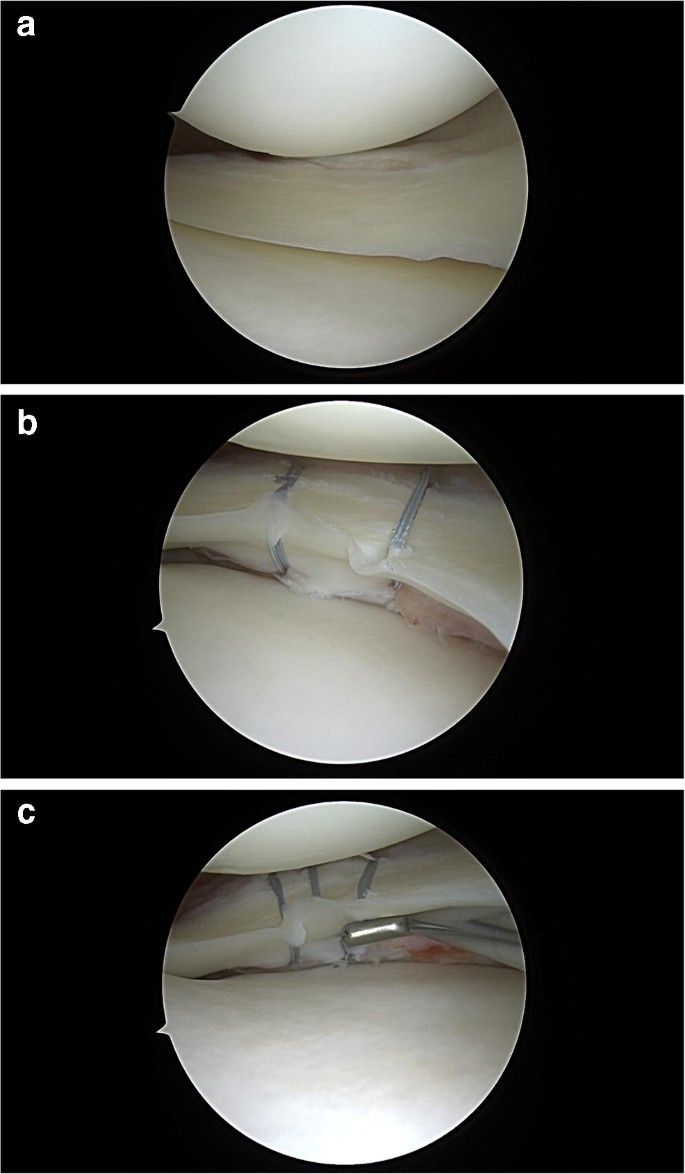

• Medicina dello Sport e Artroscopia del Ginocchio: Ricostruzione dei legamenti crociati e collaterali. Trattamento di lesioni dei menischi e della cartilagine.